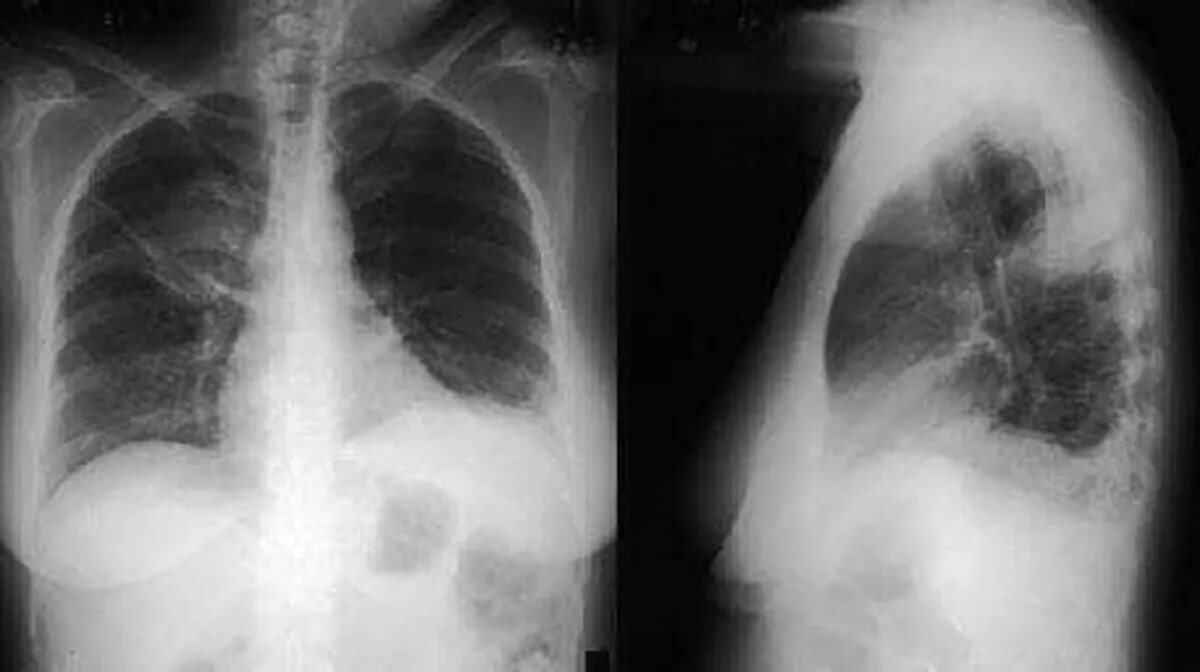

Синдром инфильтрата